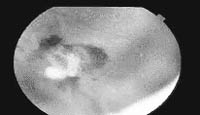

The retina of a TB patient

The most common sign of ocular TB is a choroidal mass — involvement of the layer present in the back part of the eye, also called posterior uveitis. Uveitis is a serious eye condition that may cause permanent scars. Subsequent calcification of granulomas can impede vision, and inflammation can cause irreversible damage to the eyes. Uveitis is underestimated as a cause for blindness in most surveys.